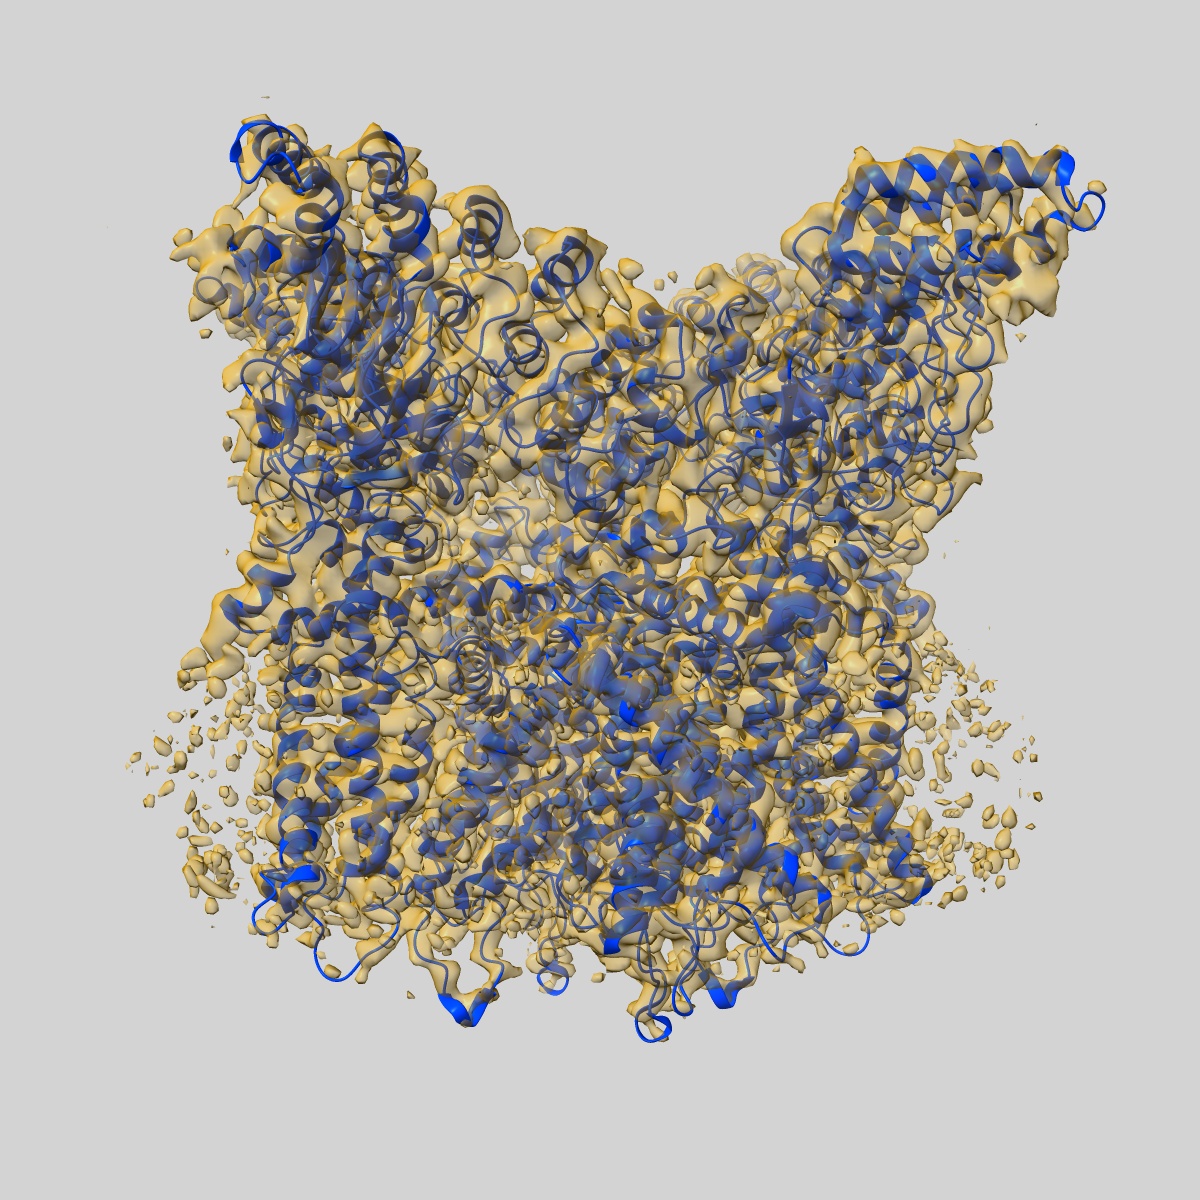

Inactivated-state cryo-EM structure of human TRPV3 in presence of tetrahydrocannabivarin (THCV) in cNW30 nanodiscs

Single-particle3.63 Å

Sample: full-length human TRPV3 in complex with THCV

Fitted models: 8v6m

TRPV3 activation by different agonists accompanied by lipid dissociation from the vanilloid site.